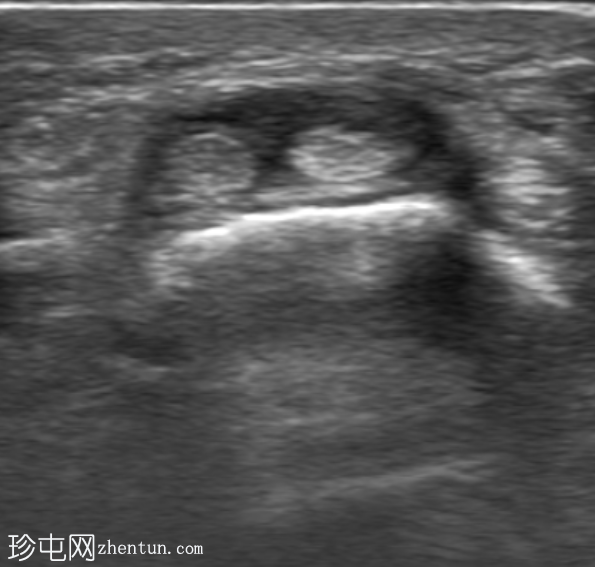

超声

横切面

第一背侧伸肌腱鞘增厚。拇长展肌 (APL) 和拇短伸肌 (EPB) 肌腱周围可见低回声液体。受累肌腱轻度增厚。未见肌腱撕裂。邻近皮质表面完整。多普勒显示轻度血流信号增多。